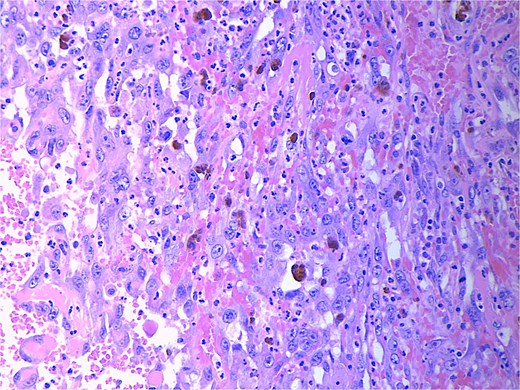

Final pathology revealed an angiosarcoma of the adrenal gland. Sections showed a predominantly hemorrhagic and necrotic mass with residual vascular forming channels within the adrenal gland (Fig. 2). Cells were pleomorphic spindled to epithelioid and atypical (Figs 3 and 4), with a mitotic count of 12/10 high-power fields. Immunohistochemistry showed positivity for ERG (Fig. 5), CD34, and focal pankeratin and negativity for SF-1, SOX10, Cathepsin-K, and chromogranin. There was no lymphatic or vascular invasion identified, and the margins were uninvolved by the tumor. The left kidney was negative for tumor, and the background adrenocortical parenchyma was benign.

High power magnification (20×) H&E showing malignant cells forming vascular channels with atypia and multiple mitotic figures.